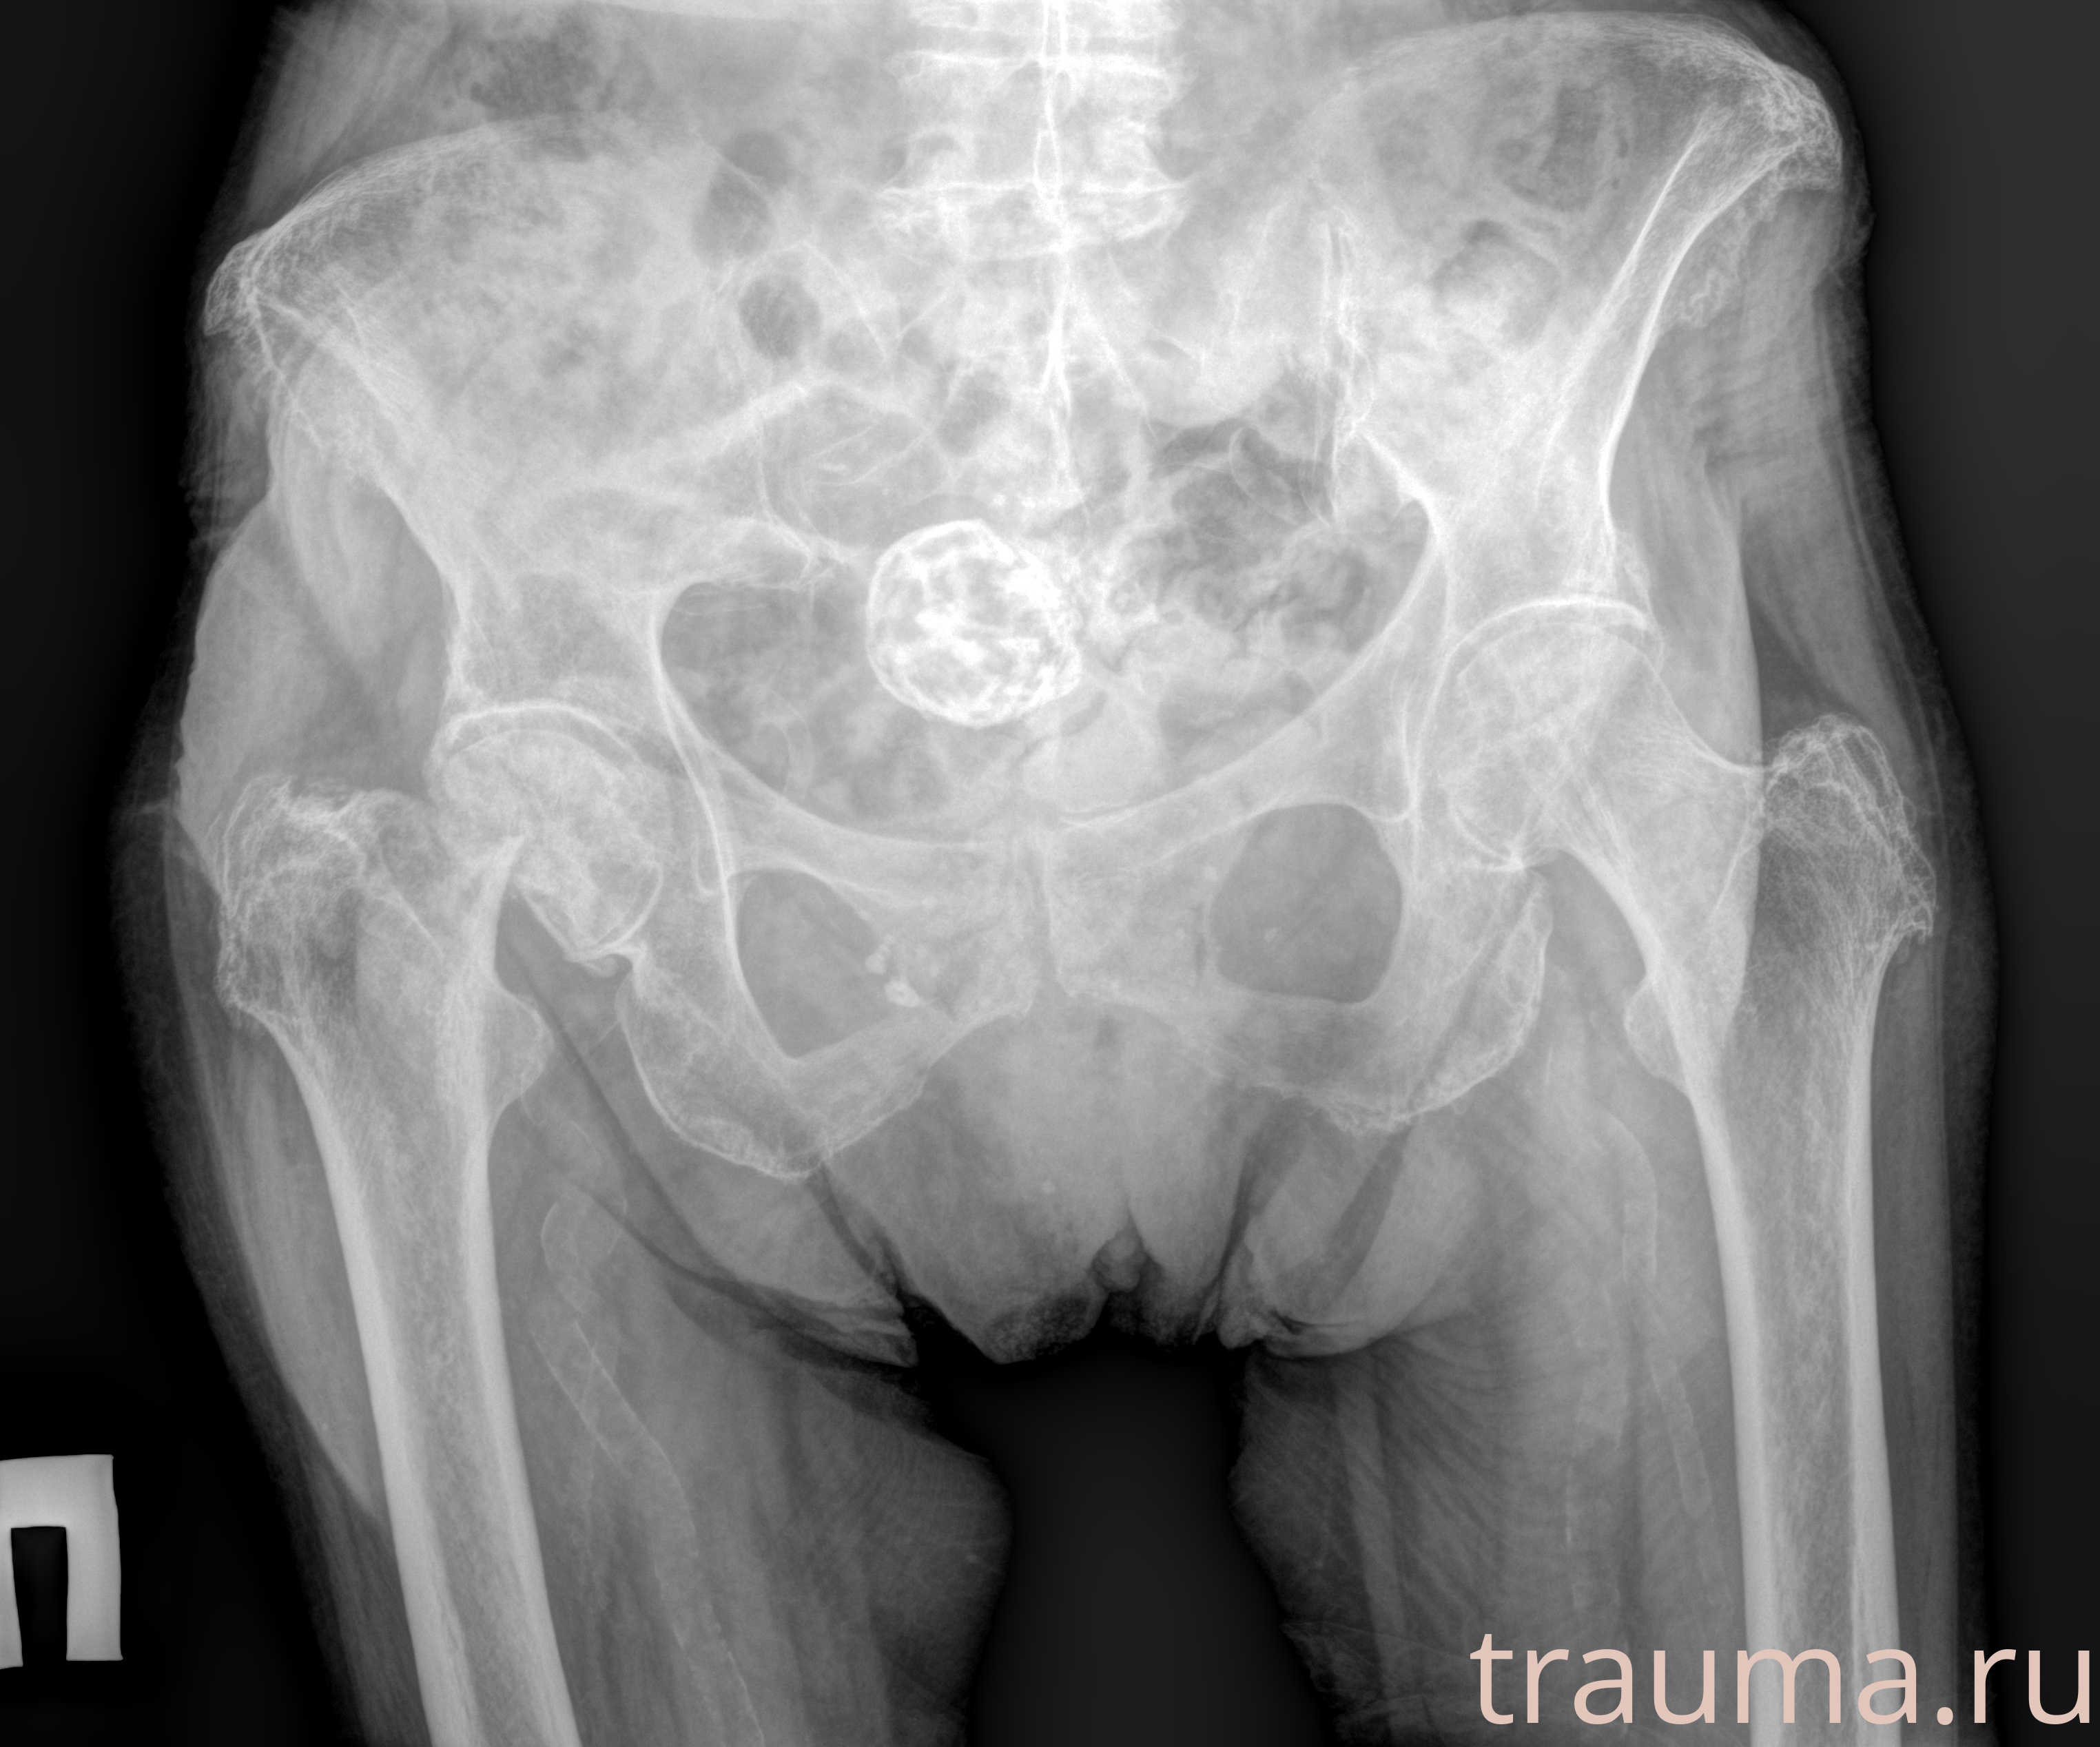

Рентгенограммы

Рентген на дому: по вашему адресу приезжает врач-рентгенолог, травматолог-ортопед с мобильным рентгеновским аппаратом, проводит диагностику травмы или заболевания, делает необходимые рентгенограммы, дает рекомендации по дальнейшему лечению. Получить качественные снимки в домашних условиях возможно благодаря уникальной методике, разработанной МосРентген Центром для института  Склифосовского